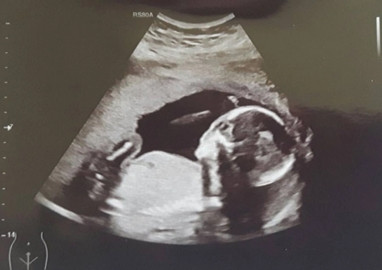

Tháng 5/2016, Emily mang thai thành công. Thai nhi nằm ở tử cung bên phải của cô và phát triển rất bình thường. Tuy nhiên, khi thai được 37 tuần, cô bắt buộc phải mổ lấy thai do tử cung quá bé so với cơ thể em bé.

Khi Richi được 1 tuổi, cặp vợ chồng trẻ tiếp tục cố gắng mang thai lần nữa. Lần này, thai nhi nằm ở tử cung bên trái của Emily.